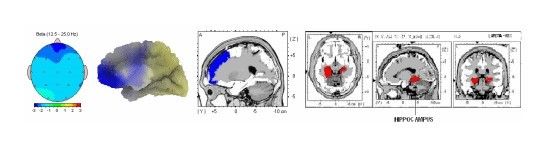

According to the images of the manufacturing and clinical testing stages, up to this stage, we had no impairment of vital signs, including breathing and heart rate, and with the feature of our refractive injections, we also prevented an increase in blood pressure, and this stage of the formulation was truly an amazing idea.